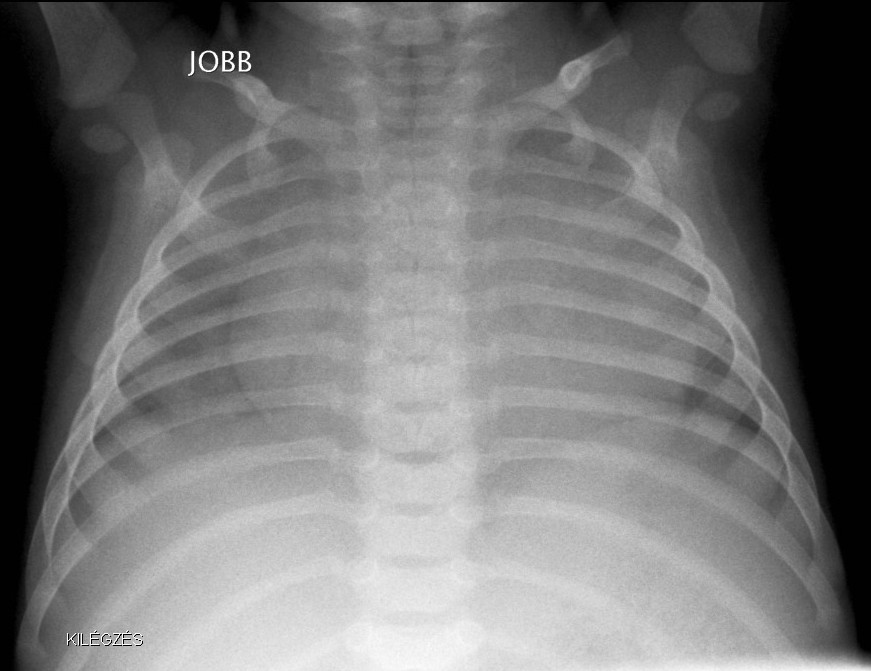

Normal newborn lungs: a newborn’s chest goes through some fundamental changes during the first days of extra-uterine life. The heart is relatively rounded, characterized by the dominance of the right side. The cardio-thoracic index taken in a mid-inspiratory state is between 0.55-0.62. Expiratory state can lead to diagnostic mistakes.

Bony thorax: the ribs are horizontal and the sagittal and horizontal diameters of the chest are very close to each other.

1. a. Expiratory state: the transparency of the lung is diffusely decreased.

Image

1.b. Inspiratory state, the lung is transparent, the heart is normal sized. Ribs run horizontally in infants.